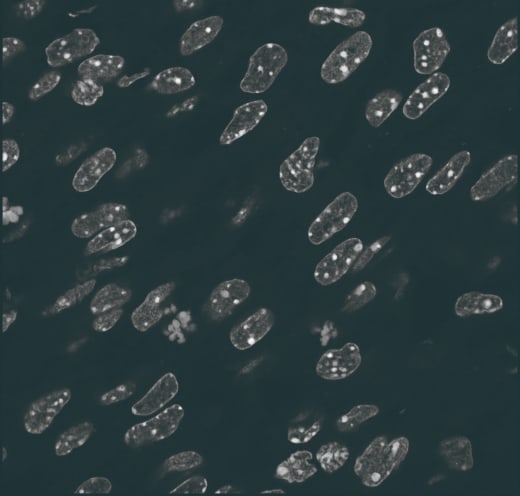

- Phenotypic Screening

- MoA / toxicity prediction via cell painting

- Automated Micronucleus Test Evaluation